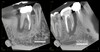

Poorly filled root canal with persistent apical pathology – diagnosis?

• Therapia endodontica defectiva

• (failed endodontic treatment).

• Treatment: Retreatment or extraction

* Periodontitis periapicalis chronica granulomatosa * (Chronic granulomatous apical periodontitis) → Well-defined apical radiolucency, loss of lamina dura

* Periodontitis periapicalis chronica cum fistula * (Chronic apical periodontitis with fistula) → Gutta-percha point tracing to apex